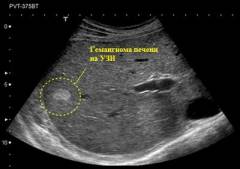

Ультразвуковое исследование (УЗИ)

Ультразвуковое исследование – безопасный, не имеющий противопоказаний метод, позволяющий определить наличие объемных образований во внутренних органах, а также выявить наличие каверн в кожных и подкожных гемангиомах. Современные аппараты для УЗИ довольно компактны и просты в применении, что позволяет провести диагностическую процедуру прямо в кабинете врача.

Метод основан на принципе эхогенности – способности различных тканей организма отражать звуковые волны, при этом степень отражения будет различной в зависимости от плотности и состава ткани. Отражаемые волны регистрируются специальными датчиками, и после компьютерной обработки на мониторе формируется изображение исследуемого органа, отражающее плотность и состав различных его структур.

Показаниями к проведению УЗИ являются:

- определение структуры гемангиомы (кавернозная или капиллярная);

- определение глубины расположения гемангиомы;

- подозрение на гемангиомы внутренних органов (печени, почки, селезенки и другой локализации).

- уточнение размеров опухоли при планировании хирургической операции.

При помощи УЗИ может быть выявлен:

- Капиллярный компонент гемангиомы. Представляет собой мелкие участки средней или повышенной эхогенности (густая сеть капилляров в большей степени, чем окружающие ткани, отражает звуковые волны), с неоднородной структурой и нечеткими контурами.

- Кавернозный компонент. Каверна представляет собой полость, заполненную кровью. Плотность крови, а, следовательно, и ее способность отражать звуковые волны, меньше, чем у густой капиллярной сети, поэтому на УЗИ каверны определяются как участки пониженной эхогенности (на фоне гиперэхогенной капиллярной сети), округлой или овальной формы, размерами от 0,1 до 8 – 10 миллиметров.

На основании данных УЗИ можно предположить наличие гемангиомы во внутреннем органе, однако для установки окончательного диагноза требуются дополнительные исследования.